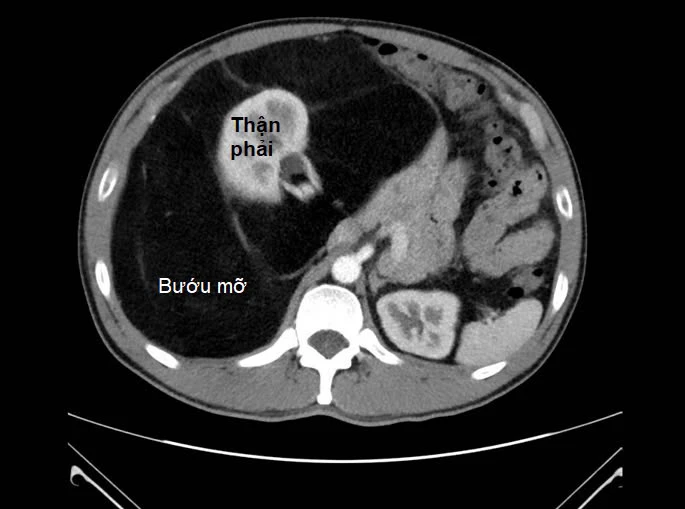

Kết quả chụp CT bụng của bệnh nhân cho thấy có khối bướu mỡ khổng lồ choán toàn ổ bụng. Ảnh: BVCC

Bác sĩ chuyên khoa 2 Nguyễn Phúc Minh, Trưởng khoa Ngoại tiêu hóa, người trực tiếp phẫu thuật cho anh T, cho biết kết quả chụp MRI bụng cho thấy khối bướu có đường kính lên đến 40 cm, cấu trúc tương đồng với mô mỡ, chiếm gần toàn bộ ổ bụng và bao quanh thận phải.

Nghiêm trọng hơn, khối bướu dính và chèn ép các mạch máu lớn như động mạch, tĩnh mạch chủ bụng và các mạch máu lân cận làm suy giảm chức năng thận.